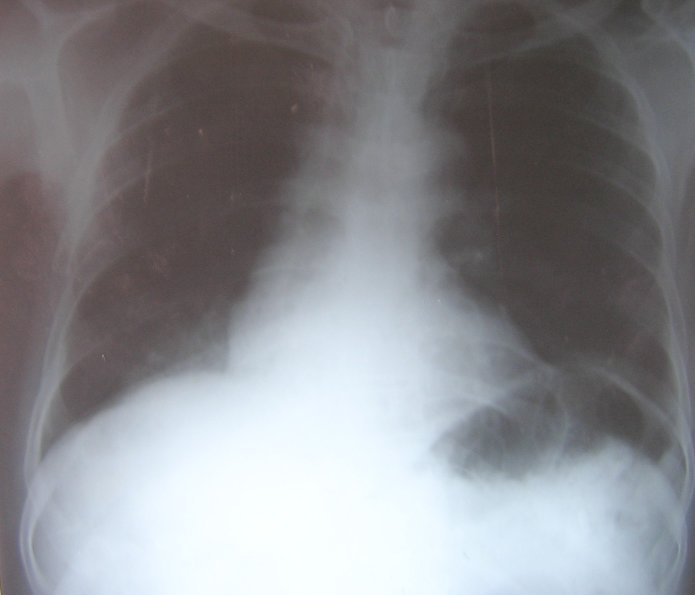

He refused surgery and was treated with cyclophosphamide, vincristine, and prednisolone. After 3 cycles of chemotherapy the patient developed an acute myocardial infarction, which was treated successfully. Further chemotherapy was not given. His chest radiograph showed clearing of the lung lesion (figure 7). Presently he is well with no recurrence and takes only low dose aspirin and isosorbide dinitrate for his ischemic heart disease.

Figure 7: Chest radiograph showing clearing of the right lower lobe opacity after chemotherapy.